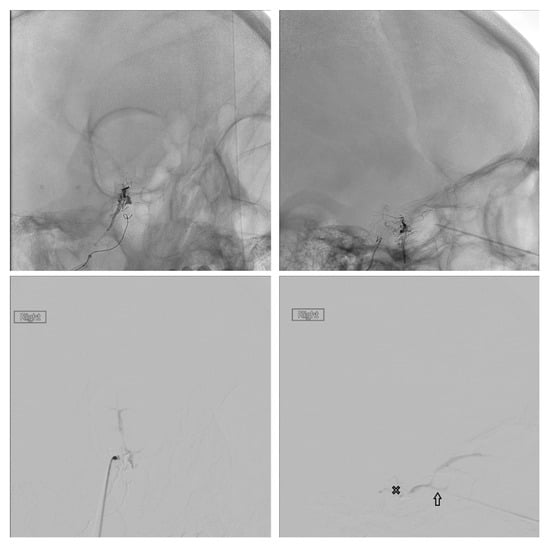

Figure 1. The common facial vein (CVF), anterior facial vein (AFV), angular vein (AV), retromandibular vein (RMV), middle temporal vein (MTV), superficial temporal vein (STV), and cavernous sinus (X) are demonstrated.

Figure 3. The middle temporal vein (solid arrow) and its connection (open arrow) with the SOV are demonstrated.

Figure 4. An example of “milking” the microcatheter along the middle temporal vein is shown.